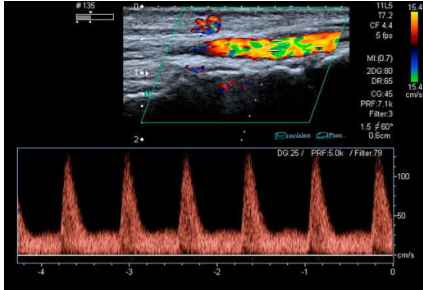

The given Doppler waveform is _____phasic, which is seen in severe stenosis of the artery: